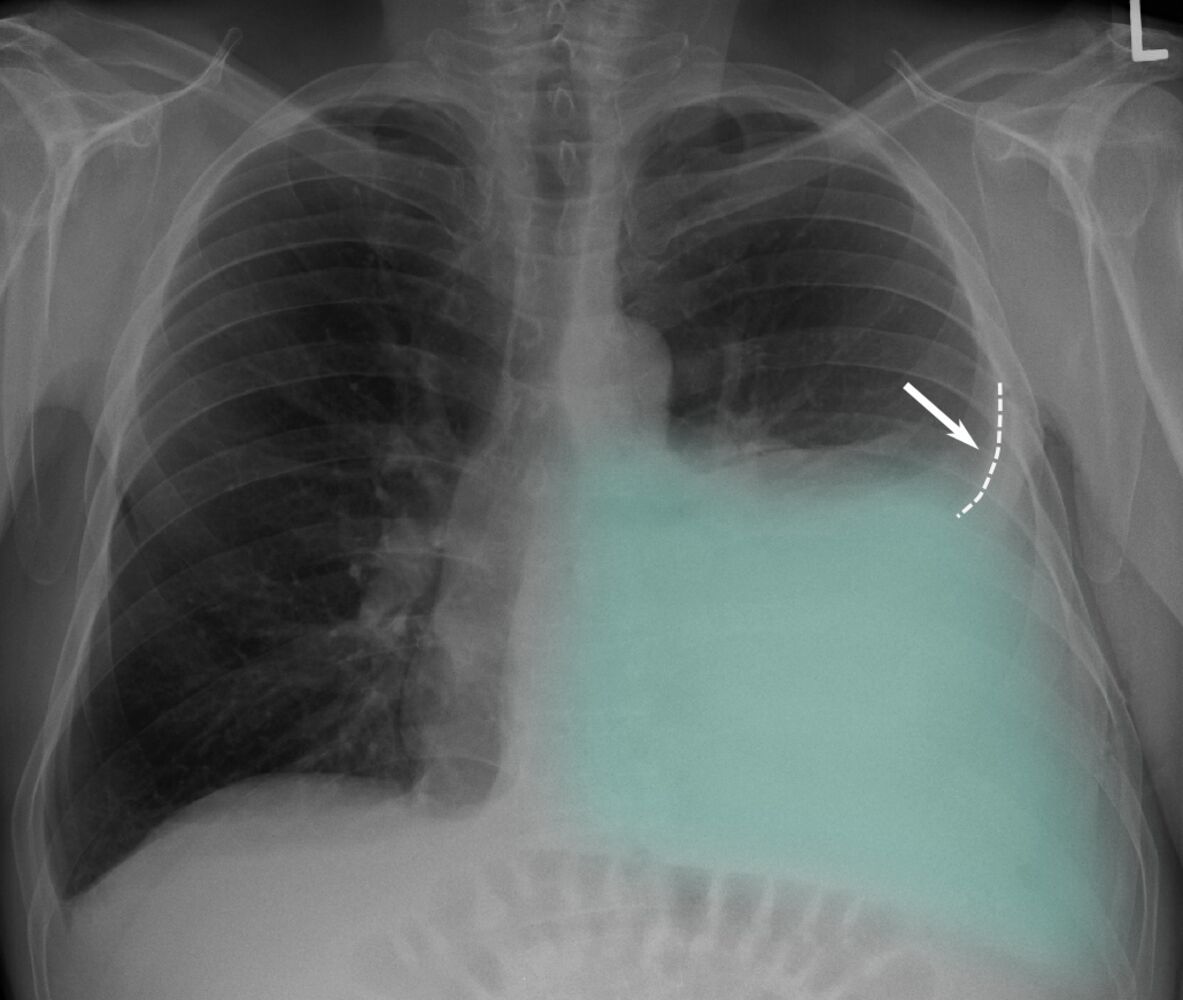

* what is an indication of pleural effusion on a chest xray? * [1]

blunted costophrenic angles